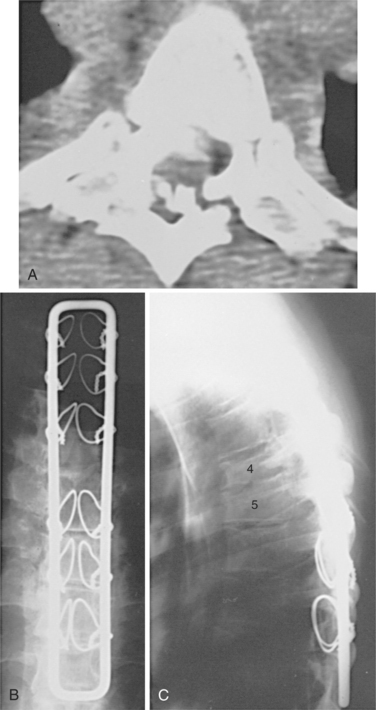

The mechanism of injury influences the type and degree of the spinal cord lesion. Fig. 34-2 shows the flexion damage that is referred to as the hangman’s fracture, related to excessive flexion. Approximately 50% of injuries come from excessive flexion of the spinal column that results in a severe neurologic disorder.18 Fig. 34-3 shows how extension can cause SCI in the elderly population. Fig. 34-4 shows vascular changes that may result from displacement of spinal components. The spinal cord is often violently displaced or compressed momentarily during an injury with forceful flexion, extension, and rotation of the spine. The vertebral body can burst and cause pressure or scatter bone fragments into the spinal cord. Fig. 34-5 illustrates this phenomenon. Complete spinal cord lesions occur in about one third of flexion injuries. With crush fractures of the vertebrae, there is a 75% chance of a complete spinal cord lesion.

Figure 34-5 A T4-T5 fracture-dislocation resulted in a complete spinal cord injury in a 30-year-old man. A, A computed tomographic scan through the injured level demonstrates marked displacement and comminution at T4-T5, with multiple bone fragments within the canal. B, A postoperative anteroposterior radiograph shows stabilization with a Luque rectangle and sublaminar wires. This instrumentation provided rigid fixation and allowed early mobilization with minimal external support. The strength of fixation could have been improved with the use of double wires around the lamina bilaterally. C, Postoperative lateral radiograph. (From Browner BD, Jupiter JB, Levine AM, et al: Skeletal trauma: basic science, management, and reconstruction, ed 3, Philadelphia, 2003, Saunders.)